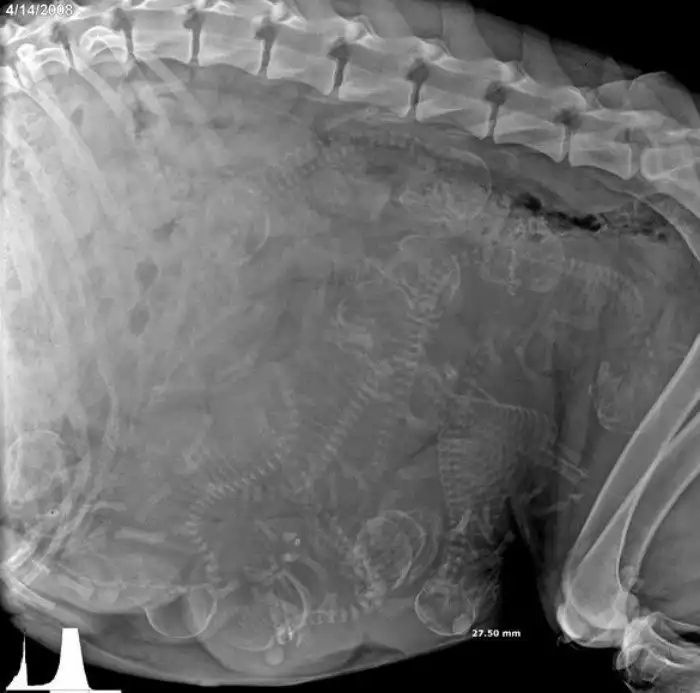

1. Беременная собака